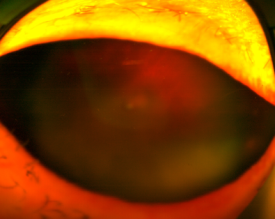

우선 백내장 상태가 더 심한 우안을 먼저 수술하기로 합니다.

이땐 수술 중 언제든 수정체낭이 터지거나 모양체소대가 끊어질 수 있기 때문에,

공막고정술로 전환할 가능성을 염두에 두고 수술을 진행해야 합니다.

(백내장수술 후 망막이 보이면 망막박리도 정도에 따라 수술방법을 정해야 했죠.)

백내장수술을 들어가보니 모양체소대약화가 전체의 1/3 정도여서,

수정체안정링(CTR)을 넣고 수정체낭속에 렌즈를 안전하게 넣었습니다.

인공수정체는 precizon 단초점토릭렌즈를 선택했는데요.

난시를 교정할 수 있고, 추후 모양체소대가 더 약해지면

바로 공막고정을 하기 수월한 렌즈이기 때문입니다.

다음날 좌안 백내장 수술도 진행하고...

수술 1주일 후 결과를 보시면

우안은 0.1 (망막박리 수술 시 실리콘 주입 상태),

좌안은 교정시력 0.8까지 회복되었습니다.

(초고도근시 환자분이라 근거리는 안경 없이,

원거리는 안경을 쓰고 보실 수 있도록 도수를 조절했어요.)